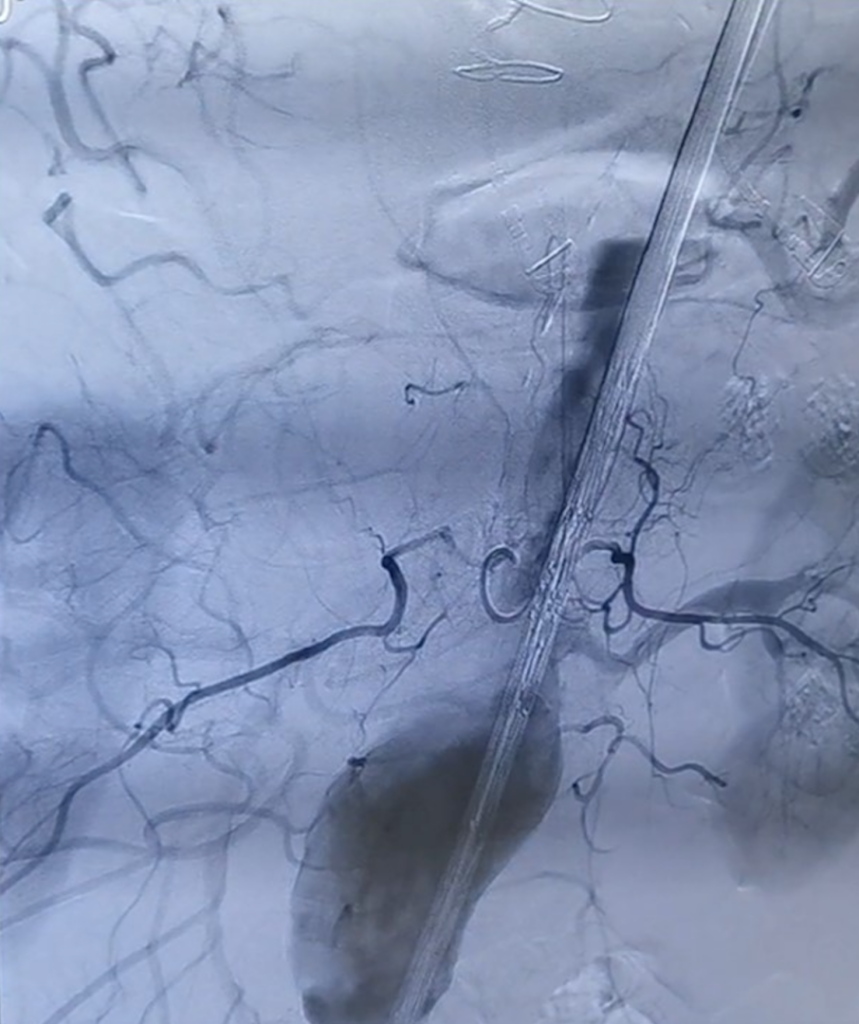

VUL Santaros klinikose pirmą kartą išsiplėtusi pilvo aorta gydyta, pritaikant individualią medicininę priemonę, mediciniškai vadinamą fenestruotą stentgraftą.

„Pirmą kartą atlikome operaciją, kurios metu implantuotas sudėtingesnis prietaisas, kuris yra fenestruotas, t.y. turi inkstų ir žarnyno arterijoms papildomas skylutes, į kurias atskirai įkišami mažesni dengti stentai, – sako VUL Santaros klinikų Radiologijos ir branduolinės medicinos centro Intervencinės radiologijos skyriaus darbuotojas dr. Andrius Berūkštis. – Prietaisas pagamintas individualiai tam pacientui pagal specialų užsakymą, kompiuterinės tomografijos vaizde tiksliai išmatavus esančius duomenis ir pritaikius pagal paciento anatomiją“. Tokio stentgrafto gamyba užtrunka 6–8 savaites.

Pasak dr. A.Berūkščio, tokios priemonės reikėjo dėl to, kad pacientui buvo išsivysčiusi pilvo aortos aneurizma, kuri plėsdamasi pažeidė (įtraukė) inksto arteriją ir žarnyną maitinančią arteriją. Procedūros tikslas – sukurti naują aortos spindį: procedūros metu į aortą įkišamas dengtas stentas, per jame esančias skylutes iškišami kiti dengti stentai, per kuriuos priteka kraujas į inkstų kraujagysles ir žarnyną maitinančias arterijas.

Operacija truko apie 3 valandas. „Procedūra sudėtinga, nes aortoje iš viso net penkios dalys turi būti sujungtos į vieną bendrą junginį, kuris atkuria sveikos aortos anatomiją. Būtina labai tiksliai nutaikyti dengto stento išskleidimo vietą, kad būtų galima per angas prakišti stentus į inkstų arterijas, daug žingsnių padaryti, kad būtų sujungtos visos dalys. Procedūra atlikta per kirkšnies arteriją, be atviro pjūvio“, – sako  gydytojas kardiologas-intervencinis kardiologas dr. A.Berūkštis ir priduria, jog po šios procedūros pacientas jau kitą dieną gali keltis ir vaikščioti, o gulėjimo ligoninėje laikas yra itin trumpas.